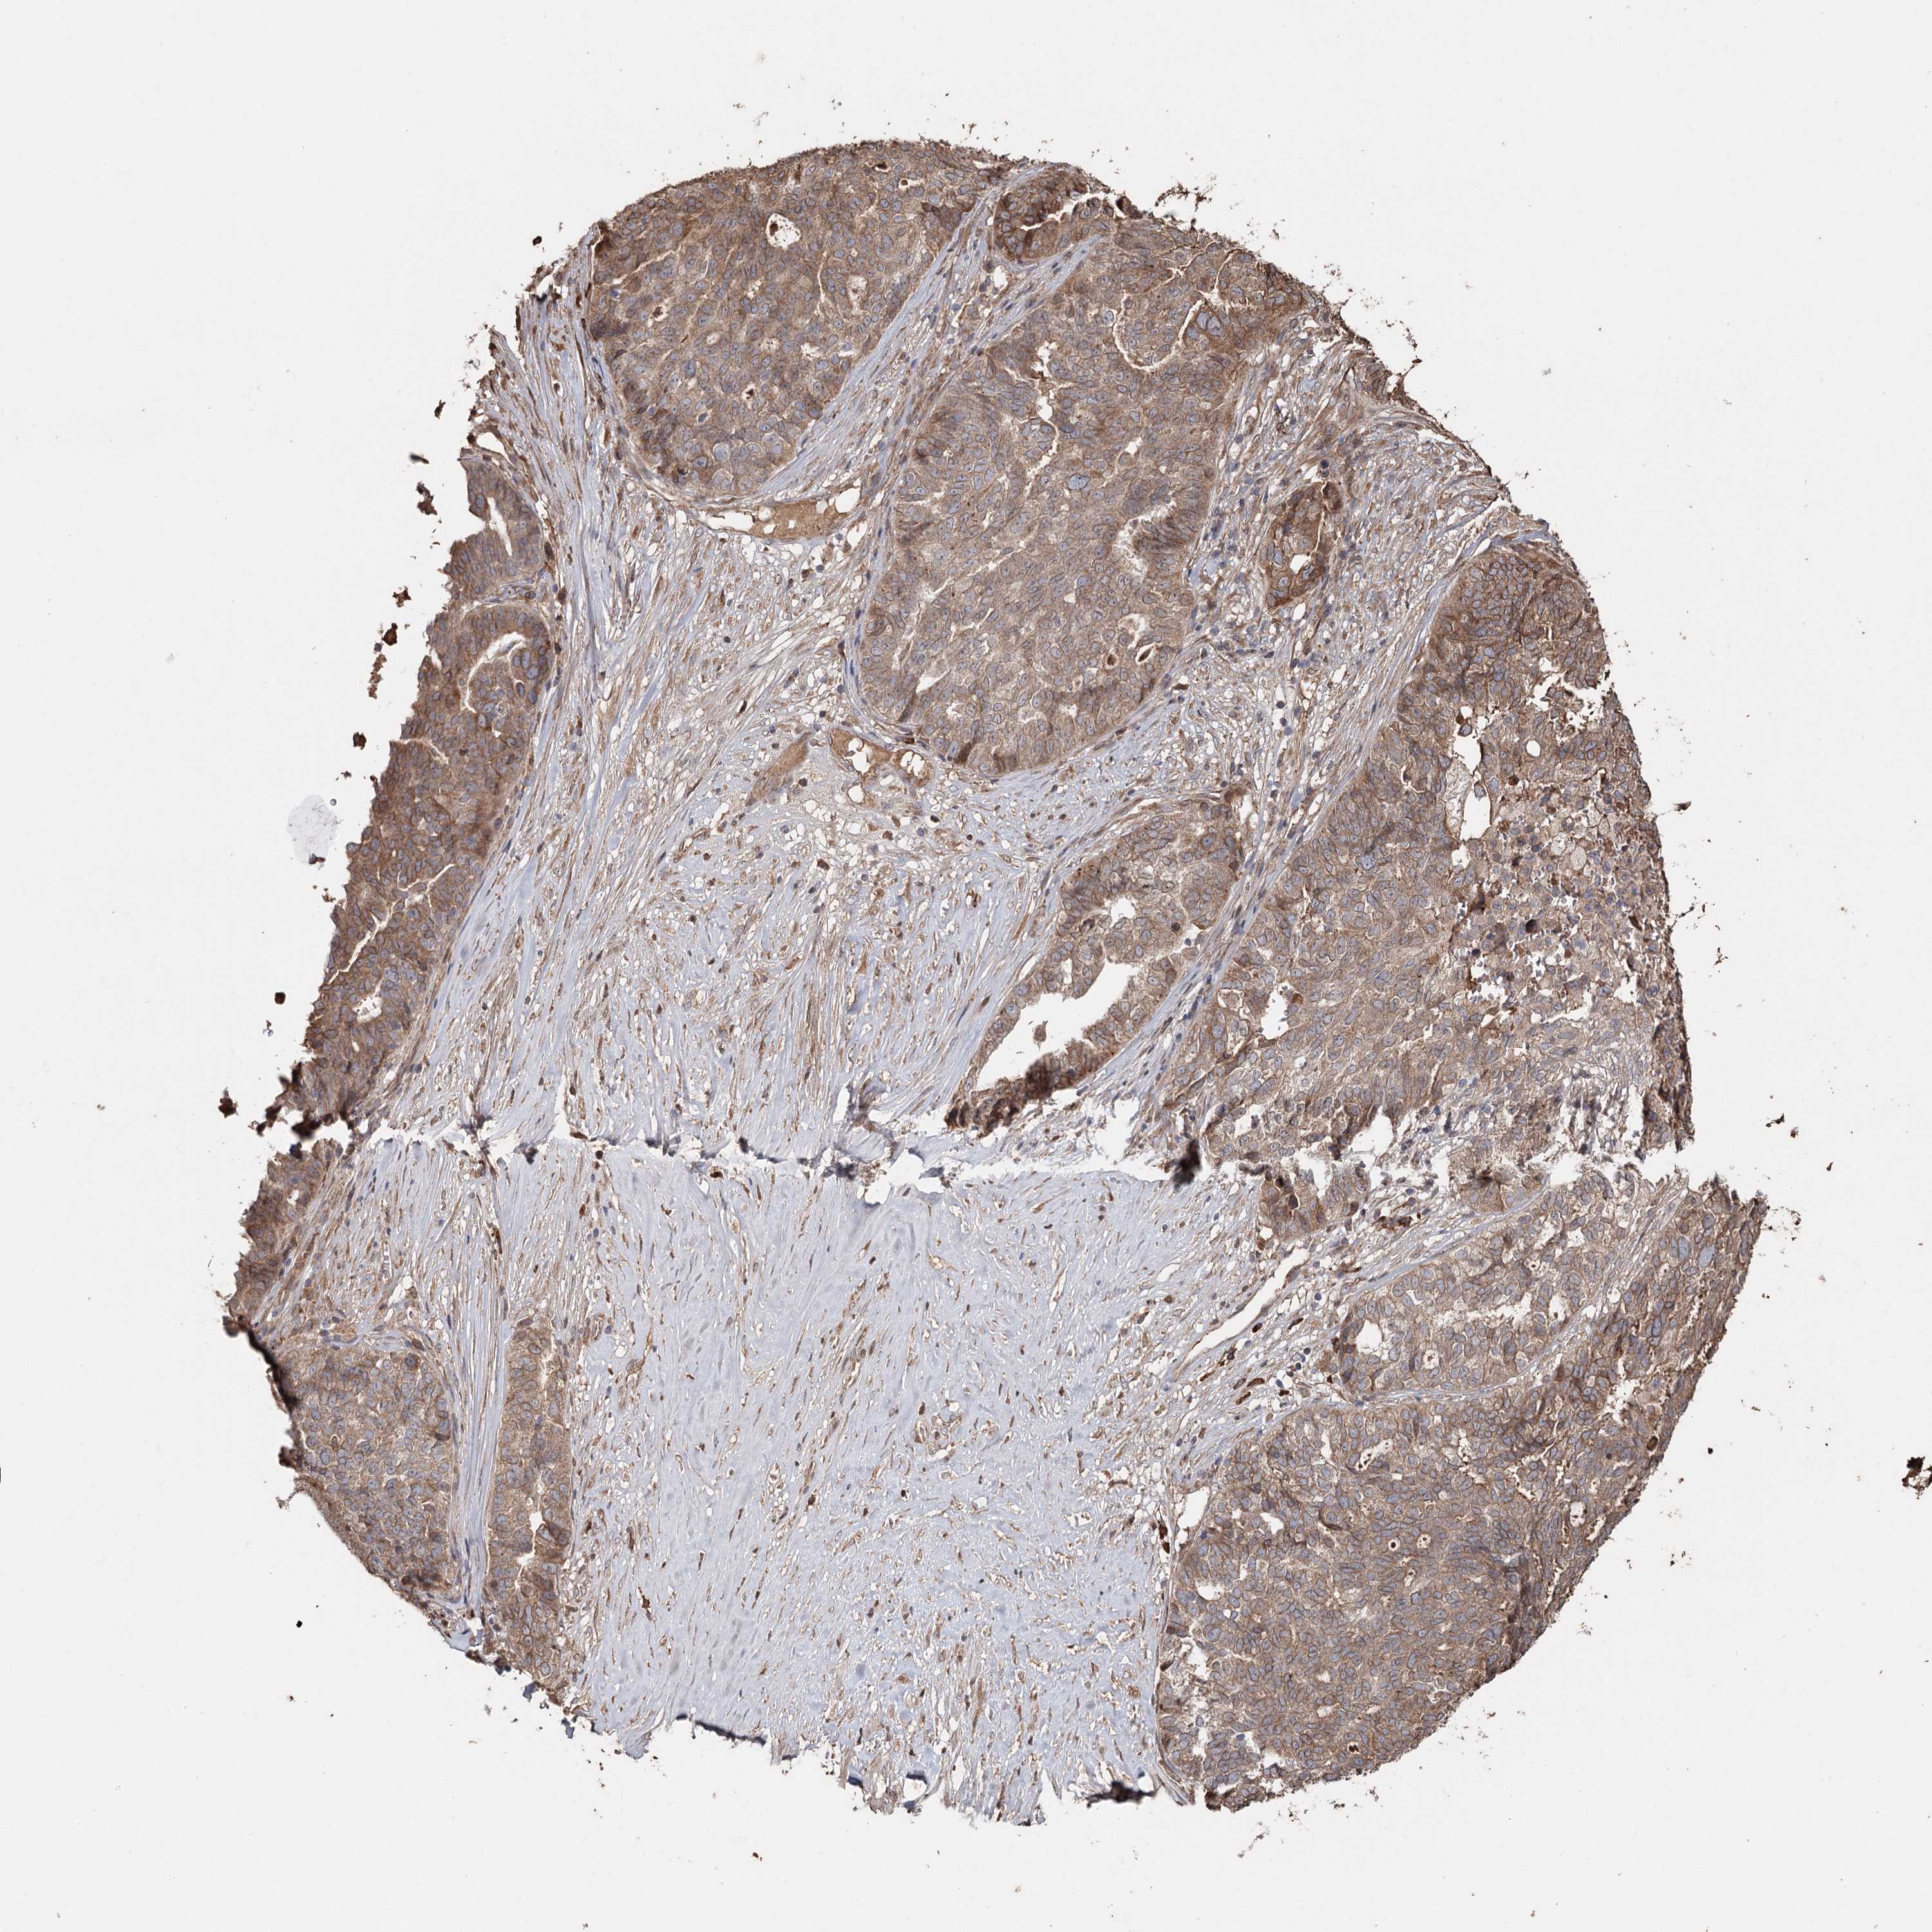

OVARIAN CANCER - Protein expressioni

A mouse-over function shows sample information and annotation data. Click on an image to view it in a full screen mode. Samples can be filtered based on level of antibody staining by selecting one or several of the following categories: high, medium, low and not detected. The assay and annotation is described here.

Note that samples used for immunohistochemistry by the Human Protein Atlas do not correspond to samples in the TCGA dataset.

Antibody stainingi

Antibody staining in the annotated cell types in the current human tissue is reported as not detected, low, medium, or high, based on conventional immunohistochemistry profiling in selected tissues. This score is based on the combination of the staining intensity and fraction of stained cells.

Each image is clickable and will lead to virtual microscopy that enables deeper exploration of all samples and also displays staining intensity scores, fraction scores and subcellular localization as well as patient and tissue information for each sample.

Antibody HPA024300

Staining

Medium

Low

Carcinoma, endometroid

Carcinoma, NOS